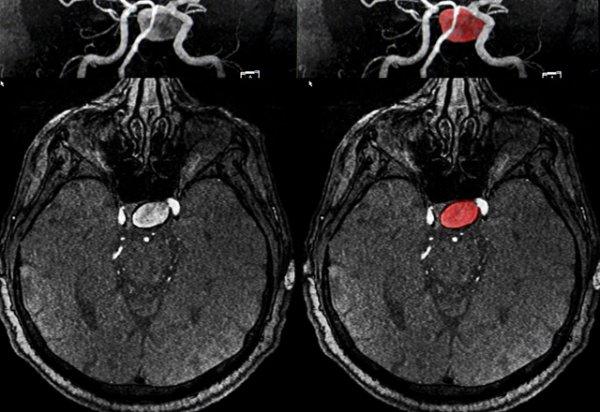

Beyin doku ve damarlarını incelemek için yapılan detaylı bir işlem olarak bilinen beyin anjiyosu, radyoloji uzmanları tarafından gerçekleştirilir.

Beyin anjiyosu, kasık damarlarından girilerek yapılır. Kataterler yardımı ile beyin içi veya beyin dışı doku tümörleri görüntülenir. Bu işlem, bazen tedavi yöntemi için de kullanılır.

X ışını ile görüntü oluşturan anjiyografi cihazları ile bu işlem gerçekleştirilir. Beyin kanaması geçiren hastaların neden bu rahatsızlığı geçirdiği de bu sayede ortaya koyulur. Bu işlemin herhangi bir zararı yoktur.